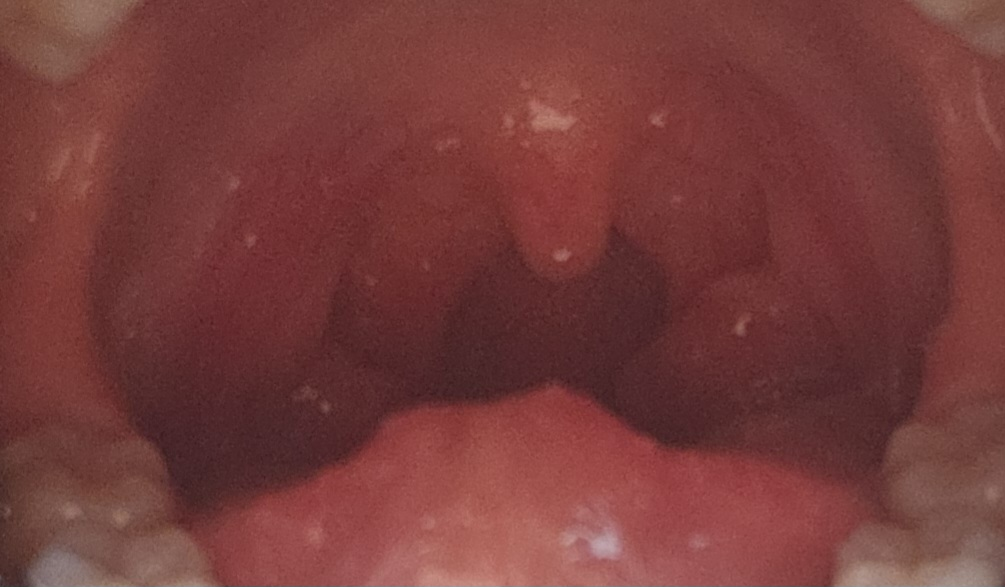

사진에 보이는 편도는 큰편이지만 아주 큰편은 아닙니다.

일단 잦은 편도염 재발이라면 수술을 해볼수가 있습니다.

현재 특별한 증상이 없다면 지켜보셔도 될것 같습니다.

정상 성인에 비해 큰편에 해당합니다.

잦은 발열 및 염증이 없다면 꼭제거를 해야하는 것은 아니지만 불편감 지속시는 이비인후과에서 제거에 대해 상의를 해보시는 것이 좋겠습니다